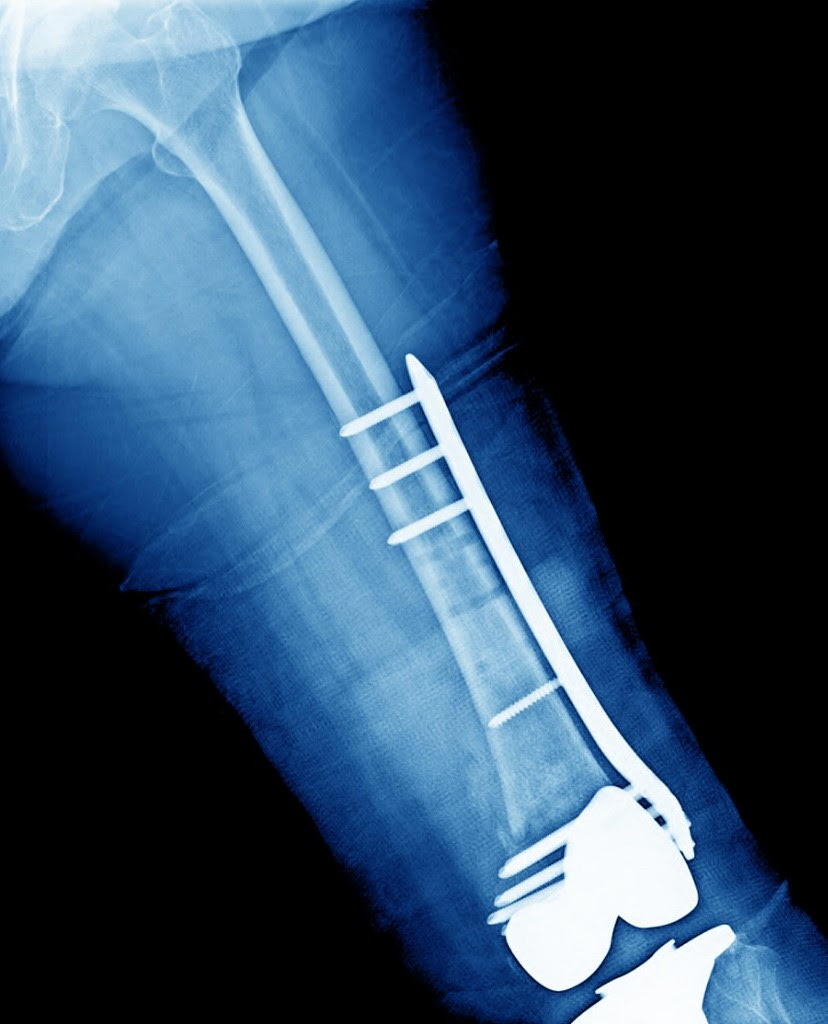

Fractures Around Hip And Knee Replacements

These fractures can possibly be treated by an orthopaedic traumatologist if the prosthesis does not have to be changed.

However, if the prosthesis is suspected of being loose it is beneficial to have a fellowship trained hip and knee Adult Reconstruction specialist to perform the procedure to likely replace the loosened prosthesis as well as repair the fracture.

These injuries can be very difficult when the prosthesis loosens from the bone combined with a complex fracture with multiple pieces and bone which is weakened like with osteoporosis.

It takes a large degree of skill to enable the proper repair of all of these components when dealing with these difficult surgeries. In most cases the patients fracture can be repaired with a new prosthesis fitted when needed.